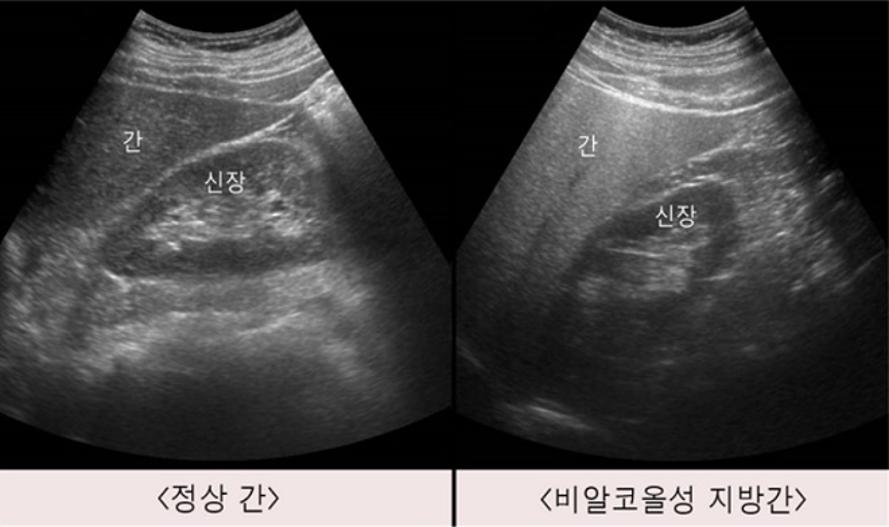

사진 : 서울아산병원

지방간은 간에 지방이 5% 넘게 쌓인 상태를 말한다. 우리나라 성인 3명 중 1명이 가지고 있을 정도로 매우 흔한데, 그 중 대부분은 비만, 당뇨, 고지혈증 등 다른 신체 질환들과 관련된 비알코올성 지방간이다.